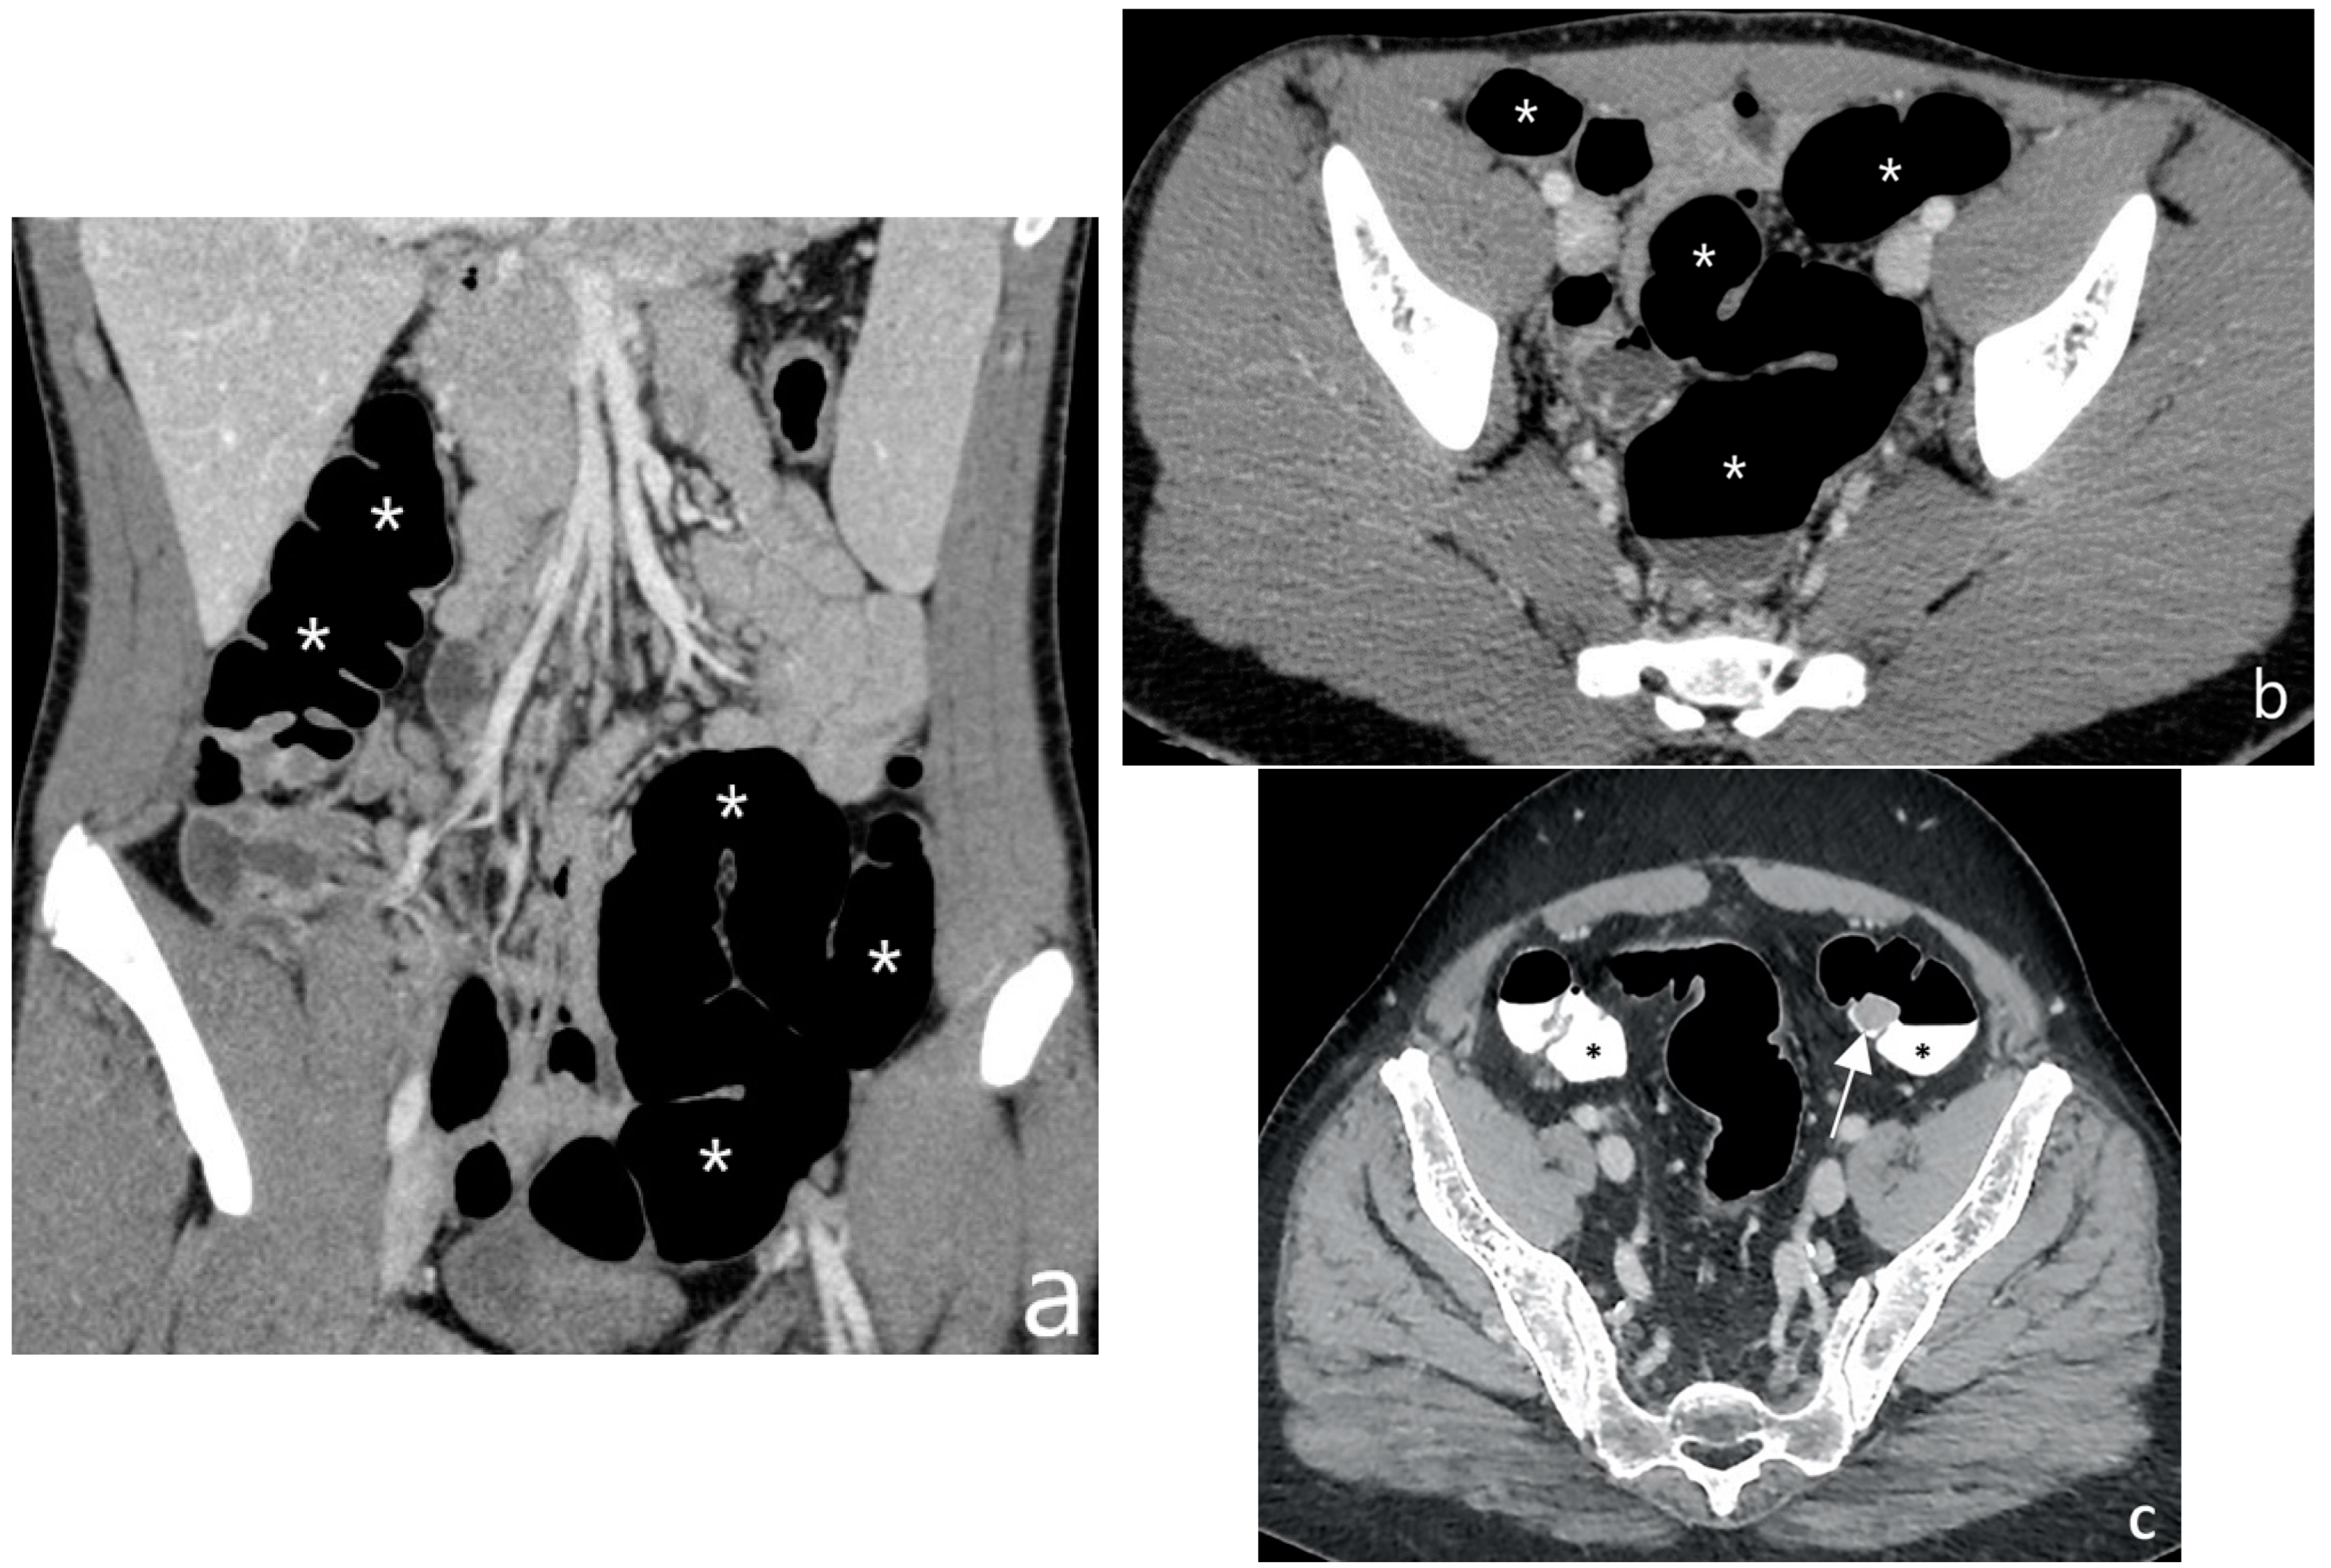

7. How Does Imaging Help Defining Disease Extension and Localization?